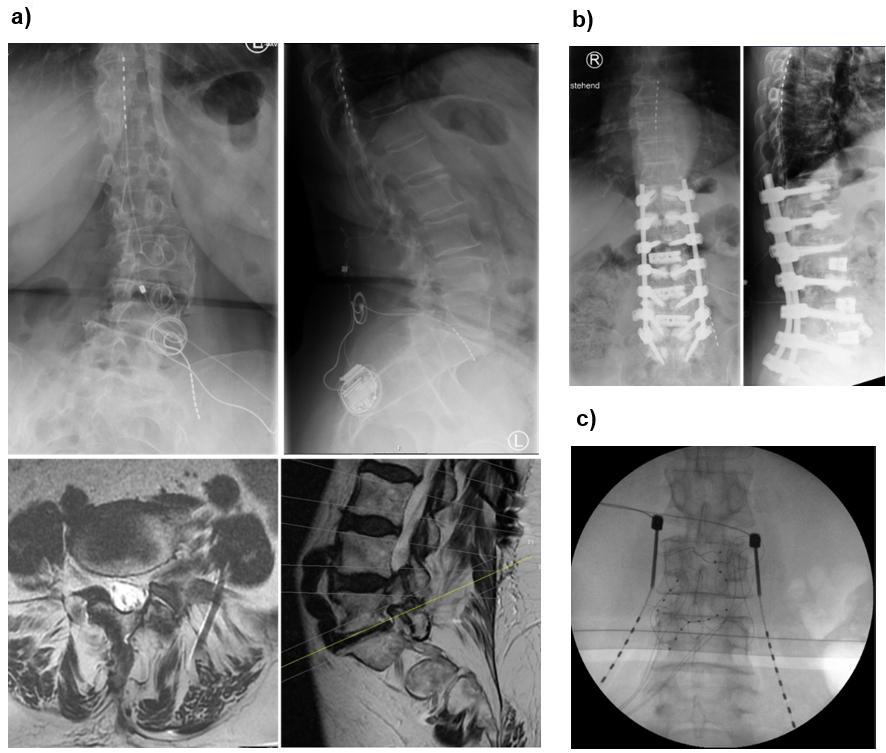

Xtra4 is particularly well-suited for patients with challenging anatomical or postoperative conditions. This includes individuals with radicular pain caused by foraminal stenosis (primary or post-surgical), epidural fibrosis, extensive scar tissue, or spinal hardware that complicates or prevents the placement of epidural leads (Figures 1a and 1b). It also represents a viable option in cases where DRG-S has failed, even if residual DRG-S leads remain in the spinal canal. In such scenarios, Xtra4 offers a safe and effective alternative that circumvents the limitations of traditional epidural approaches (Figure 1c).

Figure 1. Representative cases demonstrating the suitability of Xtra4 in patients with complex anatomical or postoperative conditions. (a) Patient with residual foraminal stenosis after spinal surgery and progressive scoliosis, experiencing worsening leg pain unrelieved by conventional SCS. Revision in 2024 included placement of a new L5 lead on the left, combined with SCS. MRI shows foraminal stenosis in axial and sagittal views; axial image highlights the L5 lead in relation to the psoas muscle and nerve. (b) Patient with challenging postoperative anatomy and radicular pain in the left L3 region; a DRG lead was contraindicated due to prior surgery and scarring. (c) Patient referred with prior two DRG revisions, presenting with lead migration of DRG leads.